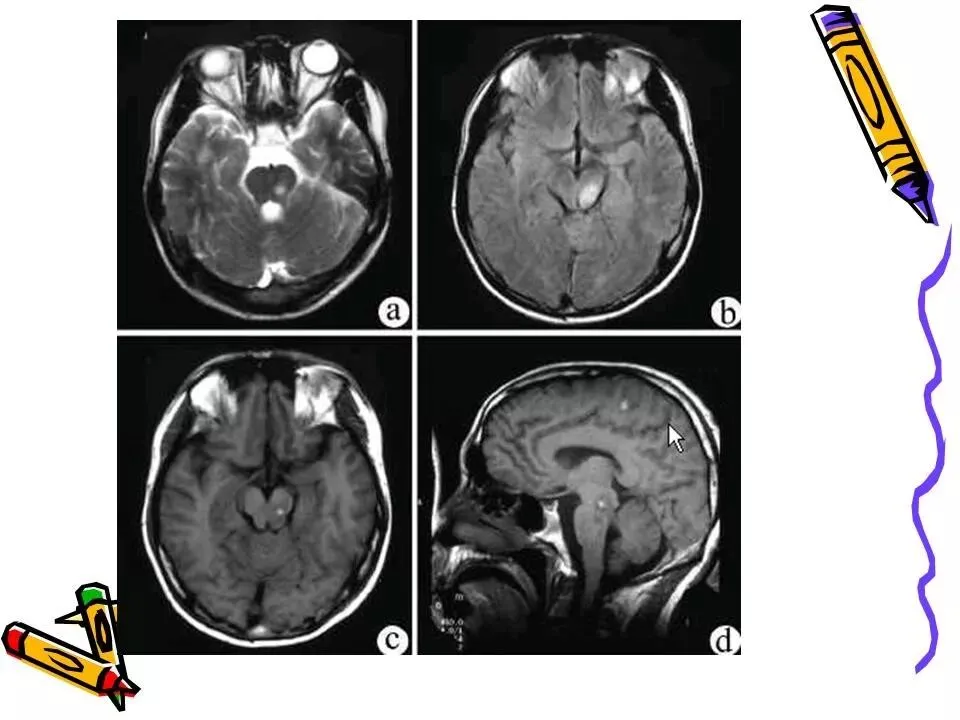

>常见颅脑外伤CT诊断(PPT)

常见颅脑外伤CT诊断(PPT)